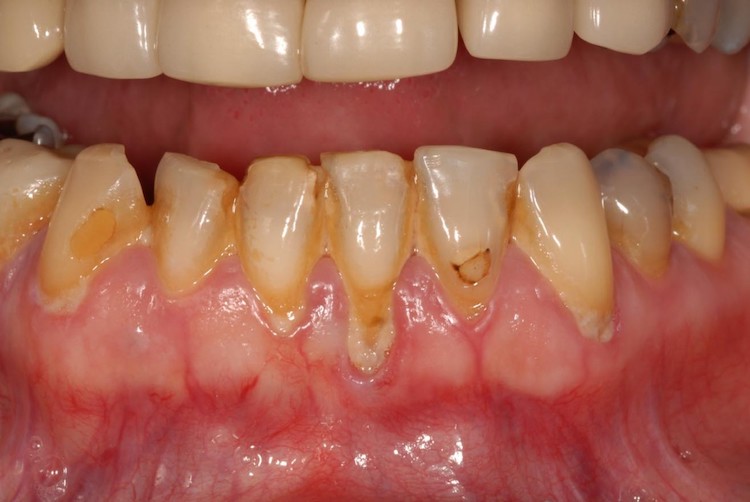

- Gây viêm nha chu, tụt nướu: Nếu không được loại bỏ kịp thời, cao răng sẽ tích tụ gây viêm nha chu, làm suy yếu mô nâng đỡ răng và dẫn đến tụt nướu.

- Ảnh hưởng đến thẩm mỹ của hàm răng: Cao răng tích tụ lâu ngày khiến răng bị ố vàng, xỉn màu, mất thẩm mỹ.

- Mức độ 3: Cao răng dày đặc, gây tụt nướu, viêm nha chu và có thể làm tổn thương đến xương ổ răng.